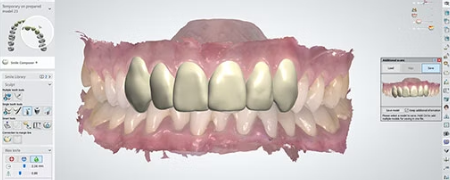

- 3D 검사장비와 6단계 정밀 진단

- 정밀구강 디지털 슬라이드 및 인상채득

- 의료진 협진 회의를 통한 정밀 진단

- 지르코니아 보철물 사용

- 지르코니아 보철물을 사용한 임플란트를

최장 10년 간 사후관리